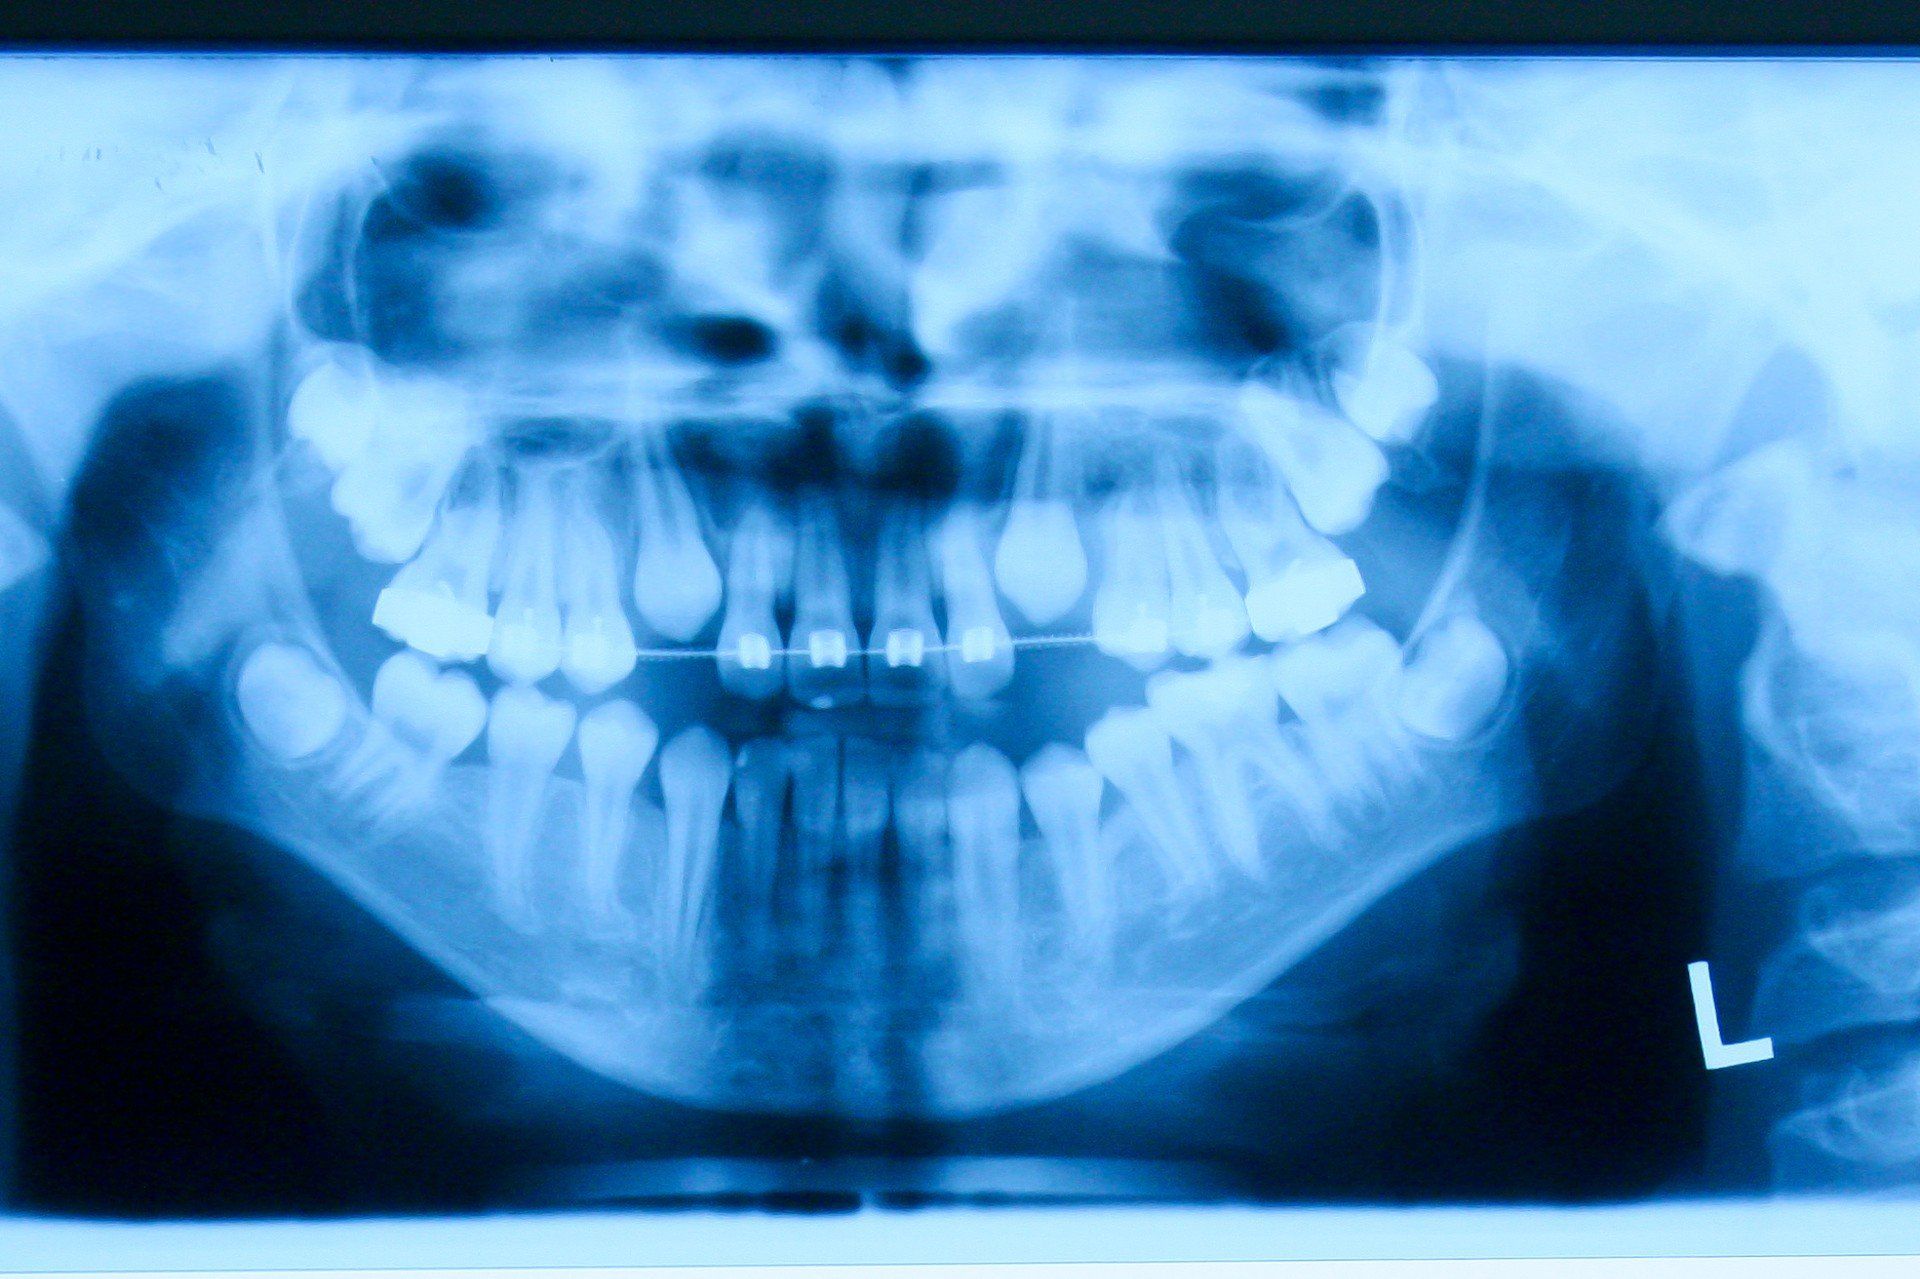

• Leczenie protetyczne - 4 września 2029 r - Konstantynów Łódzki, ul. Mikołaja Kopernika 2

• Leczenie ortodontyczne dla dzieci - 12 kwietnia 2029 r - Widawa, Rynek Kościuszki 11